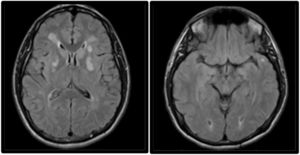

MRI study performed 2 weeks after symptom onset. Axial non-contrast FLAIR sequence showing persistent hyperintensity of the lesions affecting both lenticular nuclei, predominantly in the left hemisphere. The image also reveals hyperintensities in the subcortical white matter of both temporal poles, a typical finding in CADASIL.